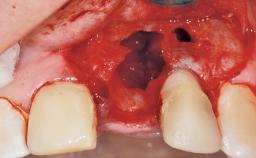

A 30-year-old female patient was referred to the office for the treatment of tooth 11. Her chief concern at the initial visit was to inquire, “Why is my tooth pink?” Upon clinical examination, it was determined that tooth 11 had a previous history of trauma and that the clinical crown had become noticeably pink in color as a result of internal resorption. This diagnosis was confirmed radiographically, indicating a large radiolucency involving the central and distal portions of the clinical crown. It was determined that restoration of this tooth was not possible, and that extraction was indicated. The presence of a mid-line diastema, which the patient wanted to reproduce, directed the treatment plan for tooth replacement utilizing a dental implant.

Placement Protocol Immediate implant placement

Tooth Site Maxillary incisor or canine

Socket Morphology Single-root socket

Socket Integrity Sufficient, with intact bone walls

Bone Volume Sufficient, with intact walls